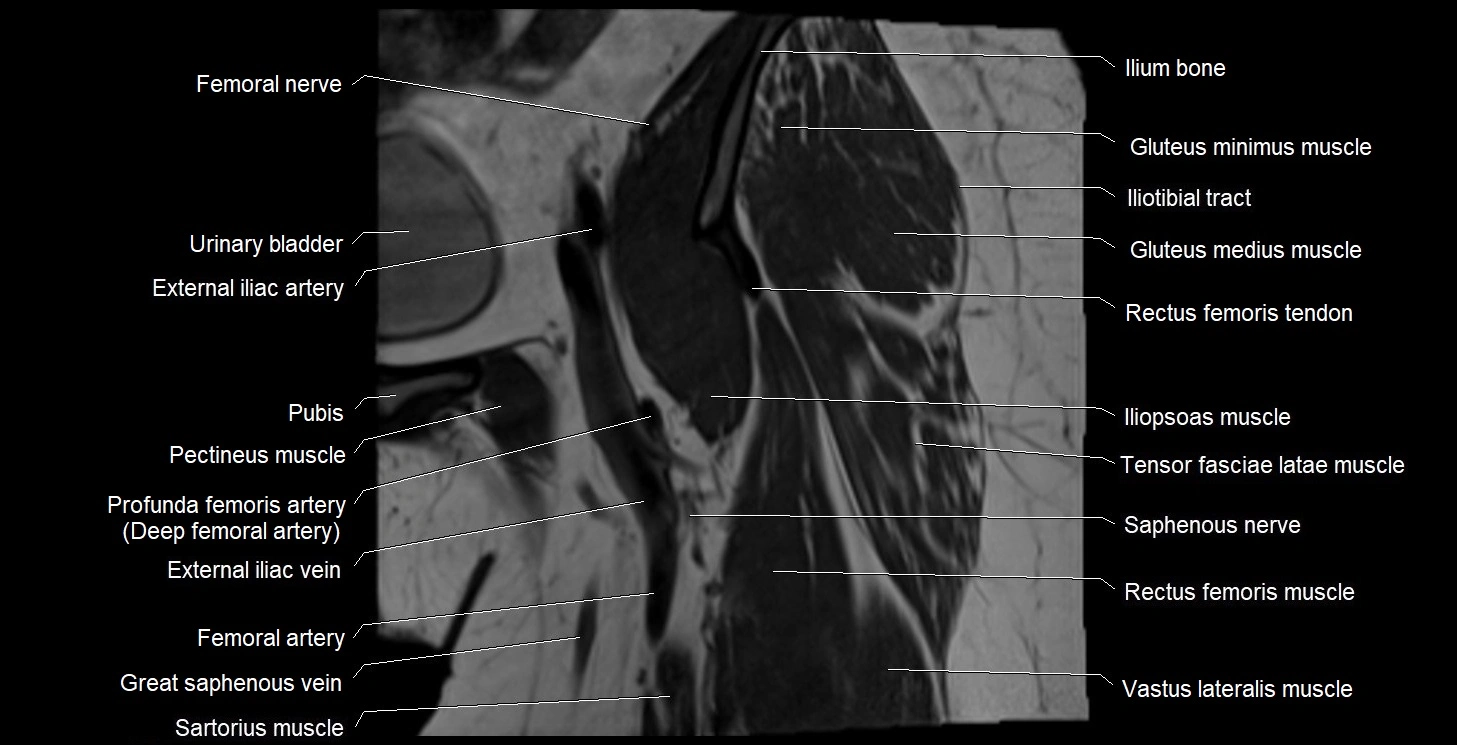

- External iliac artery

- External iliac vein

- Femoral artery

- Femoral nerve

- Femoral vein

- Gluteus medius muscle

- Gluteus minimus muscle

- Iliopsoas muscle

- Iliotibial tract

- Ilium bone

- Pectineus muscle

- Rectus femoris muscle

- Rectus femoris tendon (Proximal tendon of rectus femoris)

- Saphenous nerve

- Sartorius muscle

- Tensor fasciae latae muscle

- Urinary bladder

- Vastus lateralis muscle

- great saphenous vein